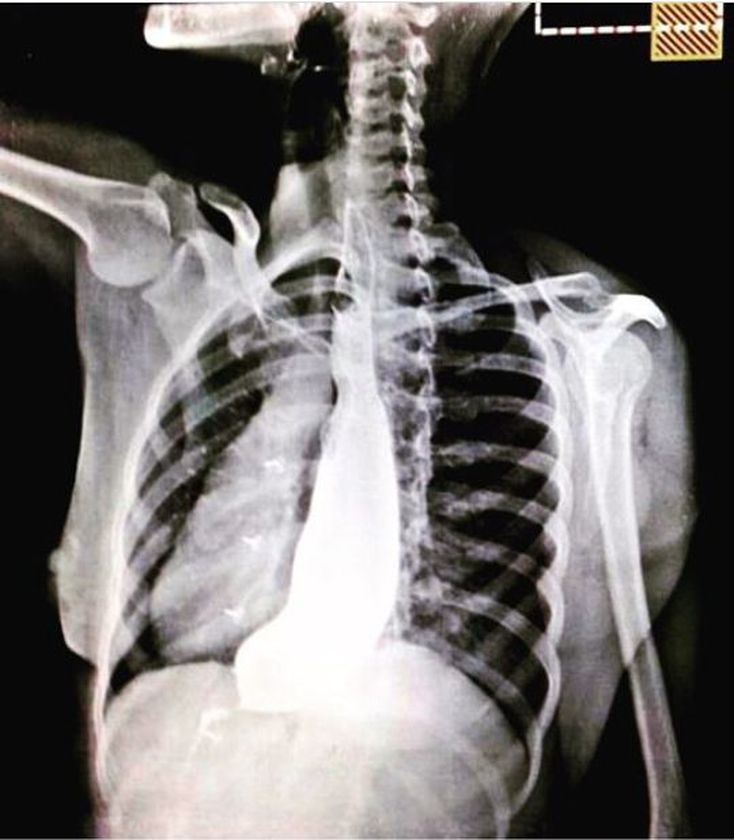

A 40 years old man came with complaints of difficulty in swallowing both liquids and solids and chest pain after eating. The following image was obtained on barium swallow examination.

"Bird beak sign"-Achalasia cardia

The X Ray is inverted. Achalasia

Bird beak sign